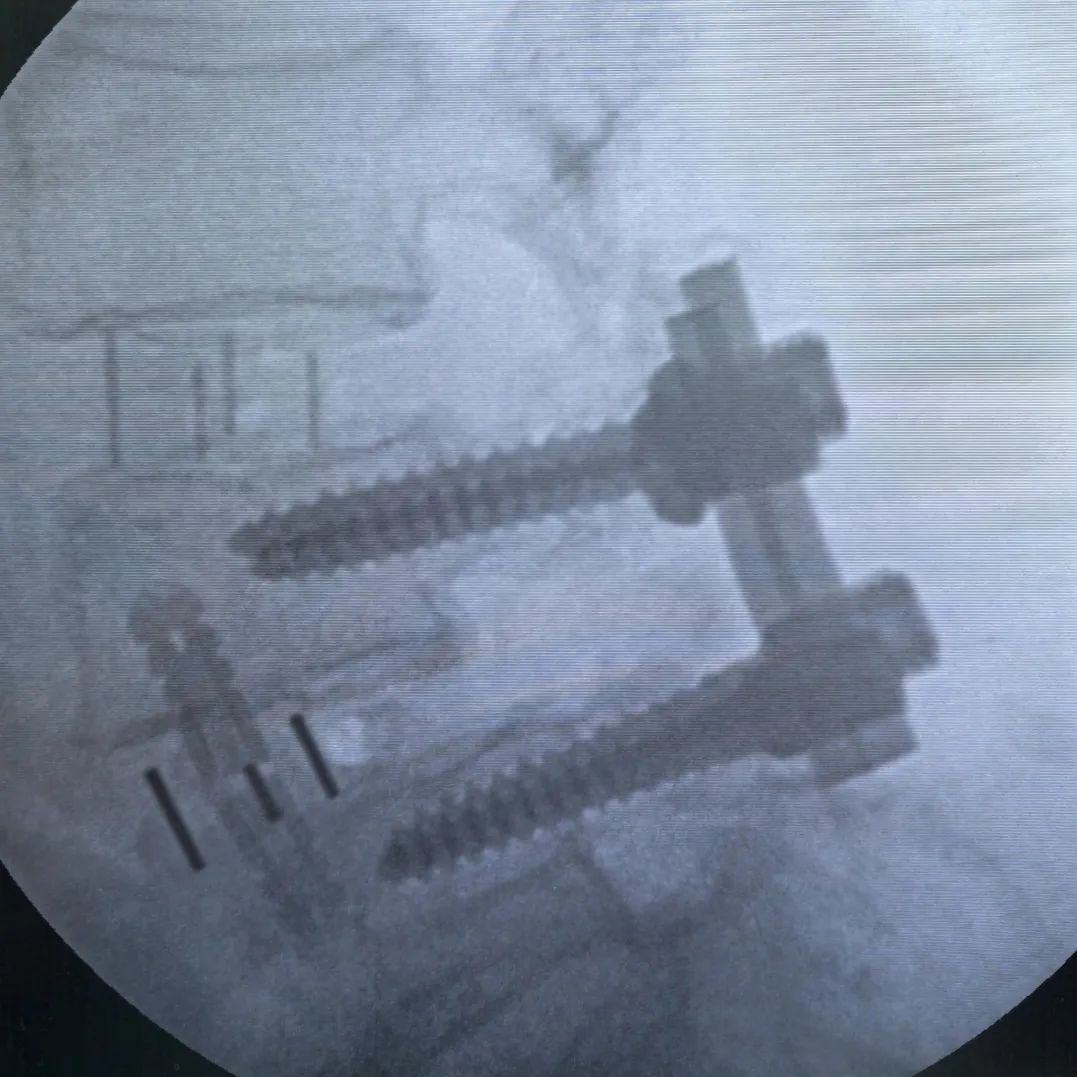

最終透視

術(shù)后一周左右,將根據(jù)情況,擇期為患者拆除、更換后路釘棒系統(tǒng)